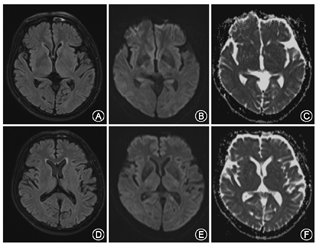

患者男性,65岁,以"右侧肢体不自主运动3 d"为主诉于2017年5月20日入我院。患者3 d前无明显诱因出现右侧肢体无意识、不规则的画图样运动,其特点为臂内旋、肘膝关节屈曲、足背屈样偏身不自主运动,鼻唇沟变浅,额纹未消失,右上肢麻木,紧张感。既往有高血压病史10余年,血压最高达160/90 mmHg(1 mmHg=0.133 kPa);否认吸烟饮酒史以及毒物接触史,否认糖尿病史以及神经变性疾病的家族史。神经系统体检示:意识清楚,语言流利,反应灵敏,双侧瞳孔等大同圆,对光反射灵敏,颈强直阴性;四肢肌力正常,足底略屈曲,左侧肢体肌张力正常,右侧肢体肌张力减弱;双侧肱二头肌、肱三头肌反射正常,双侧膝腱、跟腱反射正常,双侧巴宾斯基征、双侧霍夫曼征未引出;振动觉、位置觉、轻触觉、痛觉等未见明显异常。实验室检查结果:血清甘油三酯2.36 mmol/L(正常值0~1.70 mmol/L),血清总胆固醇6.91 mmol/L(正常值0~5.72 mmol/L),血糖、血清电解质、尿糖、尿酮体、铜蓝蛋白及甲状旁腺激素等均未见明显异常。颅脑CT平扫(64排)未见明显异常。胸片及心电图示无明显异常。颅脑MRI示:左侧额中回类圆形长T1、长T2信号影;液体衰减反转恢复序列(FLAIR)高信号影(图1A~C)。弥散加权成像(DWI)示左侧额中回皮质区类圆形极高信号影,表观弥散系数(ADC)在同一位置呈低信号影(图1D、图1E);提示该患者左侧额叶急性梗死。同时,基底神经节、丘脑以及丘脑底核未见异常信号影(图2)。因此给予患者改善循环、营养神经、联合抗血小板、降脂稳定斑块等综合治疗,另给予患者氯硝西泮0.5 mg,3次/d,口服;硫必利50 mg,3次/d,口服。出院2个月后随访,患者不自主运动,鼻唇沟变浅等症状消失,且未出现额外的非自主运动,右侧肢体麻木、紧张感缓解。